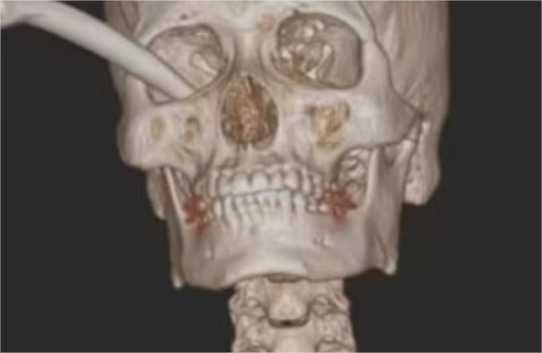

O freio não acertou a pupila e nenhum dos nervos importantes da região, mas quebrou o osso que fica abaixo do olho e perto do nariz.

O rapaz passou por uma cirurgia para retirar o freio e o tecido danificado, reparar a pálpebra e parafusar o osso quebrado. Apesar da gravidade do acidente, no retorno de seis meses após o procedimento, ele estava com a visão normal e a retina estava curada.

Os médicos escreveram no relato de caso que o olho direito do jovem estava aparentemente afundado em 5 milímetros, mas o paciente não quis continuar o tratamento.